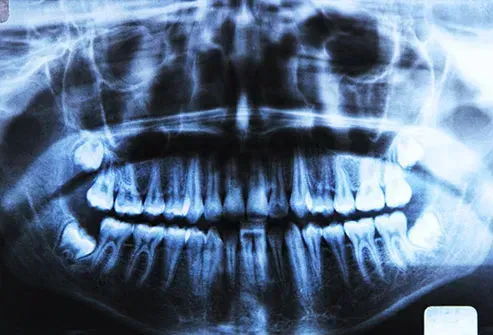

Røntgenstråler

Din tandlæge dækker dig i et bly -tæppe af en grund. Selv lave doser af røntgenstråler øger dine chancer for at få kræft, men kun med en lille mængde. Generelt jo højere dosis af stråling, jo mere risikoen er. Men der er ingen mængde af denne form for stråling, der er helt sikker. Derfor begrænser EPA, hvor meget du kan få.

Dentalfyldninger

Ring ikke til tandlægen for at få fjernet og udskiftet dine metaloptagelser. Eksperter siger, at dine nuværende er sikre. Undersøgelser har ikke fundet nogen forbindelse mellem fyldninger med kviksølv og kræft - eller nogen anden sygdom.